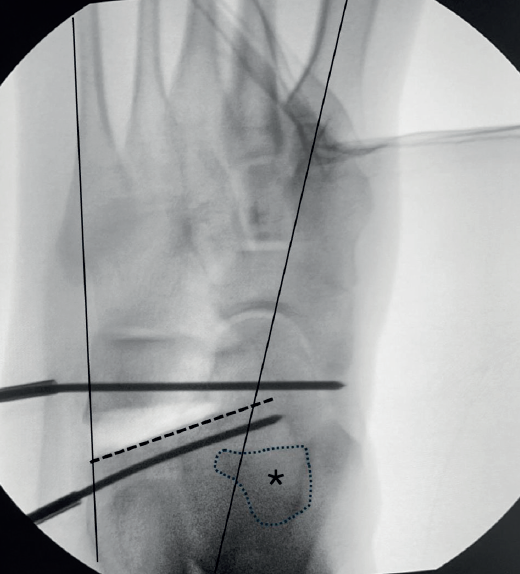

En caso de deformidad predominantemente en el plano transversal en abducto, optaremos por una osteotomía de alargamiento de la columna externa a través del calcáneo. En los casos de coalición preferimos seguir la orientación indicada por Evans modificada por Mosca. Iniciamos la osteotomía más posterior a lo descrito por Evans (15 mm de la articulación calcaneocuboidea) para disminuir la presión ejercida en la calcaneocuboidea), comenzando justo delante de la articulación subtalar sin lesionarla con dirección anterior para intentar terminar la osteotomía entre las carillas subtalar media y anterior, de forma que pasaremos por delante de la zona de coalición talonavicular (que frecuentemente se localiza en la carilla subtalar media) (Figura 1). Buscamos una corrección similar a la que realizamos en pies planos flexibles en la radiografía dorsoplantar, pero no será tan llamativa, ya que movilizamos la osteotomía y se corrige el abducto exclusivamente por el movimiento de la mediotarsiana por delante de la zona de coalición. En algunos casos, sobre todo en coaliciones talonaviculares óseas en las que el astrágalo está fijo en flexión plantar en la radiografía de perfil, observaremos que la relación entre astrágalo y calcáneo puede no cambiar, sin que esto sea un problema para la realineación.